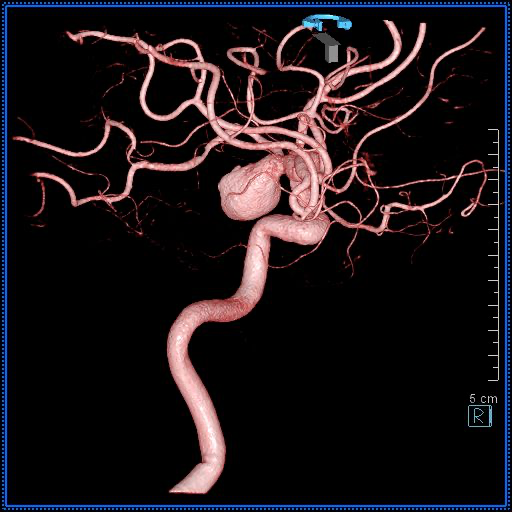

3Dワークステーション(画像解析システム)の紹介

立体的な画像診断で精密医療を実現

当院では3D画像解析システムSYNAPSE VINCENT ver6.4(Fujifilmhealthcare製)を導入し、CT・MRI・アンギオ検査で取得した画像データを立体的に再構成・解析しております。従来の平面的な断層画像に加えて、臓器や血管を3次元で可視化することで、より正確で詳細な診断と治療計画の立案を可能にしています。

3Dワークステーションの特徴とメリット

立体的な病変の把握

平面画像では判別困難な複雑な病変の形状、位置関係、周囲組織との関係を3次元で正確に把握できます。特に血管の走行や腫瘍の進展範囲の評価に威力を発揮します。

患者様への分かりやすい説明

3D画像を用いることで、病状や治療方針を視覚的に分かりやすくご説明できます。患者様とご家族の理解を深め、安心して治療を受けていただけます。

当院3Dワークステーションの強み

高性能解析システムを導入し3D画像解析を提供しています。AI画像解析技術も積極的に活用し、解析時間の短縮と診断精度を向上しています。

脳血管3D画像